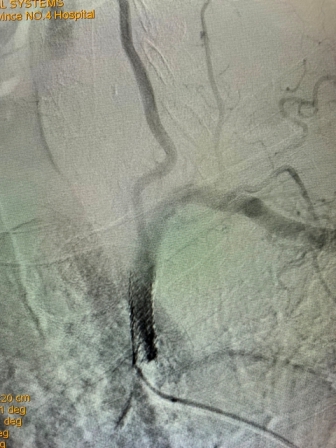

2021年8月5日,六合彩生肖神经内科神经介入专家团队成功完成首例锁骨下动脉再通介入术

(术前造影) (术后再通造影)